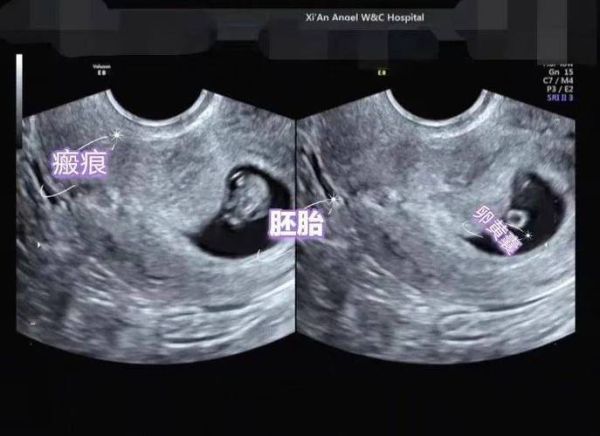

**经阴道超声** - 探头直接进入阴道,贴近子宫,图像清晰,**无需憋尿也无需空腹**。 - 适合孕周较早(<10周)或腹部脂肪较厚的孕妇。 **经腹部超声** - 探头隔着腹壁扫描,需要**膀胱作为“声窗”**把子宫顶起,图像才清楚。 - 检查前1小时喝500–800 ml水,有明显尿意即可,**不必空腹**。 - 若既想憋尿又怕呕吐,可少量进食清淡饼干,避免胃里完全空荡引发低血糖。 ---

• 5–8周:确认宫内孕,可选经阴道或经腹。经腹需憋尿,无需空腹。